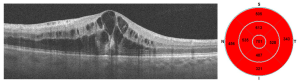

Imaging tests like fluorescein angiography and OCT.